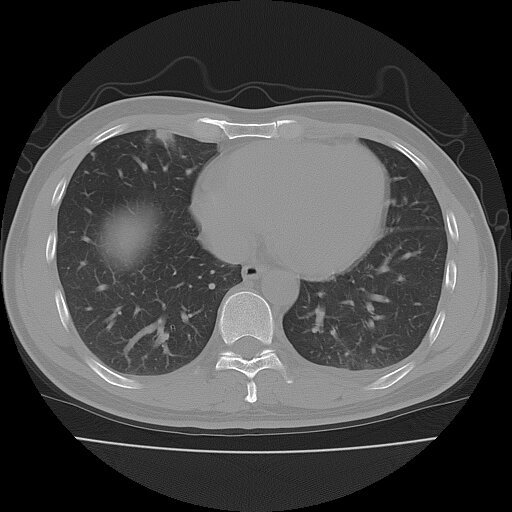

左侧胸痛,无其他病史

炎性假瘤

考虑肺内炎性肉芽肿,少量胸水。

转移瘤

考虑两肺感染性病变;建议抗炎治疗后复查。

暂考虑两肺感染性病变,左侧少量胸水;建议抗炎治疗后复查

首先考虑双肺感染性病变,左侧少量胸水,见过类似病例,抗炎后都吸收了

右侧胸膜下多发小结节——支持考虑:炎性假瘤!

警惕转移灶